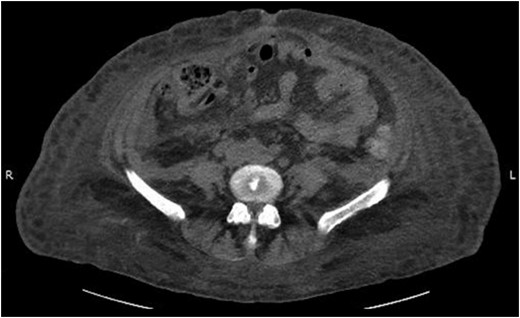

On examination she was pale, had a blood pressure of 97/52 mm Hg and heart rate of 74. On abdominal examination, she was distended and tender in all four quadrants. Her hemoglobin (Hb) was 4.7 g/dl, white blood cell count was 11.4 × 109/l and platelet count was 146 × 103/mcl. Her international normalized ratio (INR) was 1.5, which was reversed effectively with two units of fresh frozen plasma. She was transfused five units of packed cells improving her hemoglobin from 4.7 to 7.8 g/dl. An emergency contrast CT scan of abdomen and pelvis was performed which showed a large right-sided RSH extending into the space of Retzius (Fig. 1).

The following day the patient’s urine output declined progressively and she subsequently developed acute renal failure. A urinary catheter was placed but significant resistance was encountered secondary to her locally distorted anatomy from the hematoma. A repeat non-contrast CT abdomen and pelvis was therefore obtained which showed further extension of the RSH into the space of Retzius with retroperitoneal extension causing hydronephrosis (Fig. 2).

Abdominal CT scan showing the RSH extending into space of Retzius and retroperitoneum.